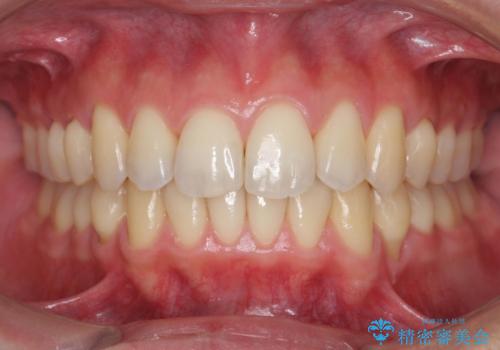

過蓋咬合・上顎前突・叢生を改善するマウスピース矯正

20時間以上のマウスピース装着、ゴムかけを遵守していただいたおかげでしっかりと噛み合わせ、がたつきの改善を行うことができました。